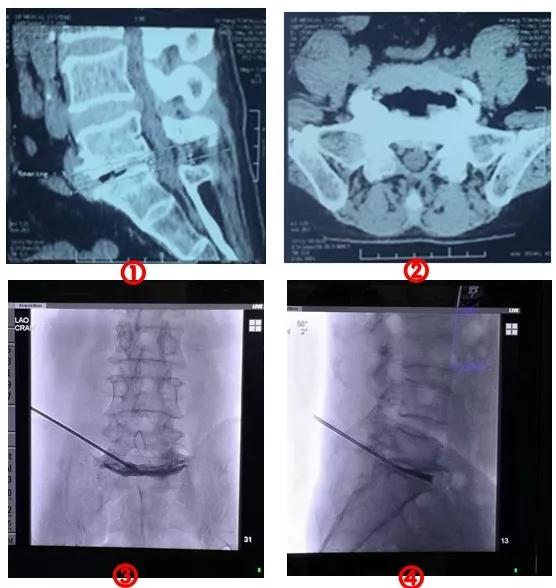

王义清主任、张延平主任根据病人病情,查阅国内外相关最新文献,经过两个科室反复论证和部署,为患者施行了西北首例“经皮骨水泥椎间盘成形术”。手术非常顺利和成功,张大爷在术后疼痛立即消失,行走正常,完全达到了预期效果。

骨二科副主任杨寅解释说:经皮骨水泥椎间盘成形术(Percutaneous cement discoplasty,PCD)可以简单的理解为在两个不稳定的、引起疼痛的腰椎之间经过精确定位微创穿刺注射入特殊药物,凝固后变成一枚“水泥楔子”撑开不稳定的腰椎,恢复腰椎的稳定,这样疼痛就可以缓解。此方法于2015年由匈牙利医生的P.P. Varga报道并命名,目前国内仅上海报道开展数例,而西北尚未见报道。

①②术前CT     ③术后腰椎正位片    ④术后腰椎侧位片